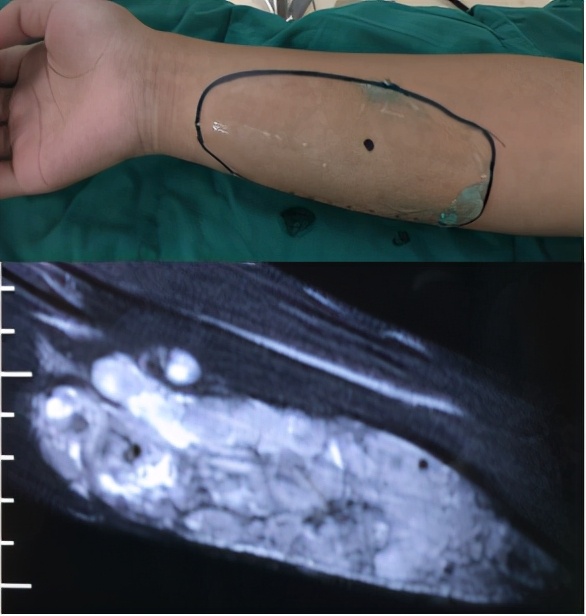

图3:术前MRI检查明确病变性质,术中超声定位穿刺点,保证良好的硬化剂注射效果